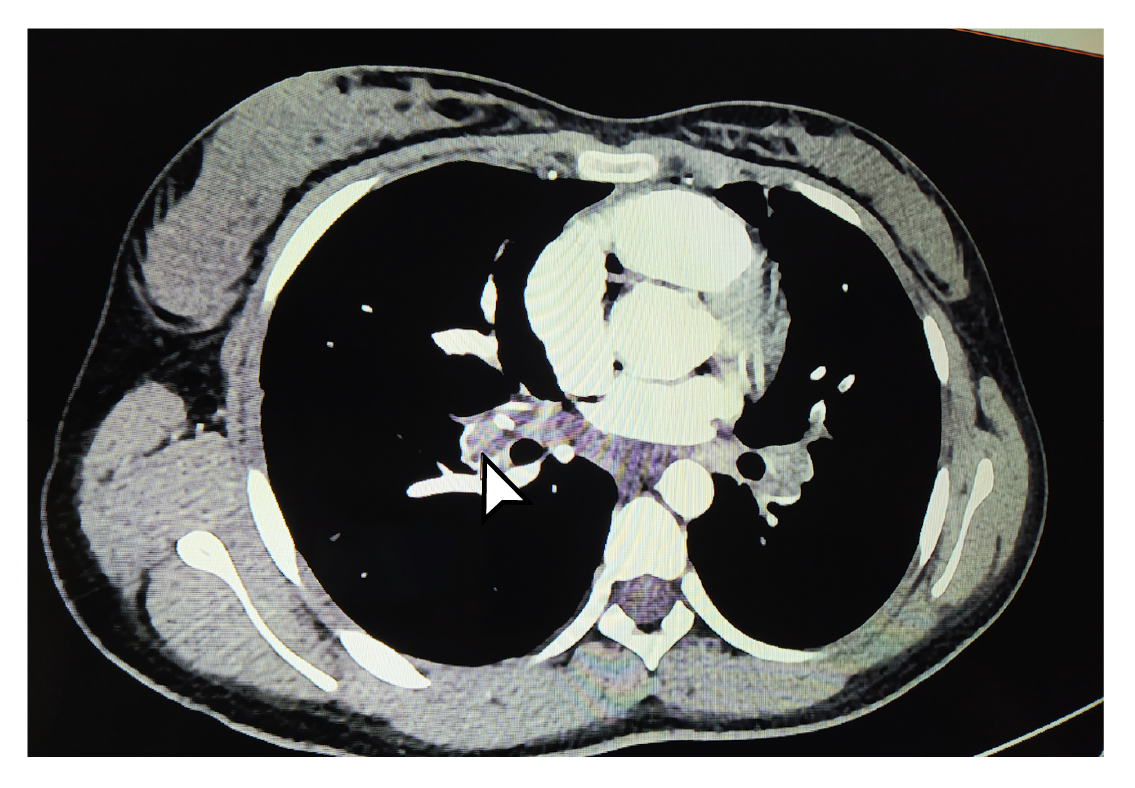

Los estudios se complementaron con tomografías de tórax y de abdomen con contraste, las cuales evidenciaron tromboembolia pulmonar grave (figuras 1 y 2) con múltiples trombos bilaterales, áreas pequeñas de infartos pulmonares, nódulos pulmonares múltiples, y embolia venosa renal bilateral con trombo que comprometía la vena cava superior. Se decidió reiniciar el tratamiento anticoagulante con heparina de bajo peso molecular, con lo cual los síntomas respiratorios mejoraron, lo que permitió dar de alta a la paciente y retomar el seguimiento por consulta externa.